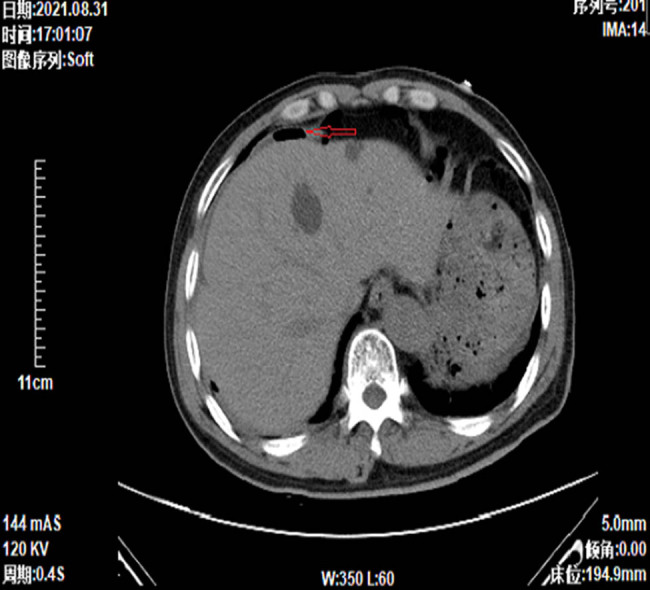

Patients with small cell lung cancer (SCLC) typically exhibit a poor prognosis, often receiving diagnoses at an advanced stage. Despite recent advances in immunotherapy, the median survival remains approximately one year. Gastrointestinal metastases from lung cancer, based on clinical experience, are exceedingly rare and associated with dire prognoses. This article details the diagnosis and management of an unusual case of SCLC with gastrointestinal metastasis. The patient's survival was notably prolonged compared to typical SCLC outcomes, providing significant clinical insight.